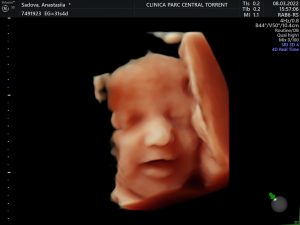

La más alta tecnología en ecografías 5D. Full HD Vision

Periodo ideal para ver la carita de vuestro bebé. ¿A quién se parecerá?

Video evolución del feto en 5D